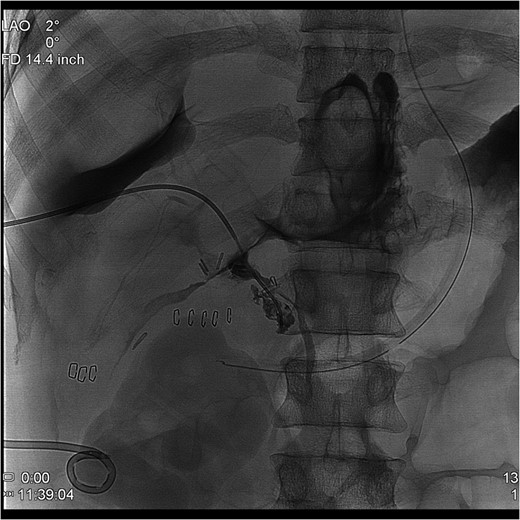

The PTC study confirmed the presence of a completely transected duct, and, fortunately, the ductal injury was traversed with a wire with entry into the distal ductal orifice and into the duodenum (Figs 4–6). Following the procedure, the patient was taken directly to the operating room for open surgical repair.

Percutaneous Transhepatic Cholangiogram showing contrast filling the distal duct following continued injection.